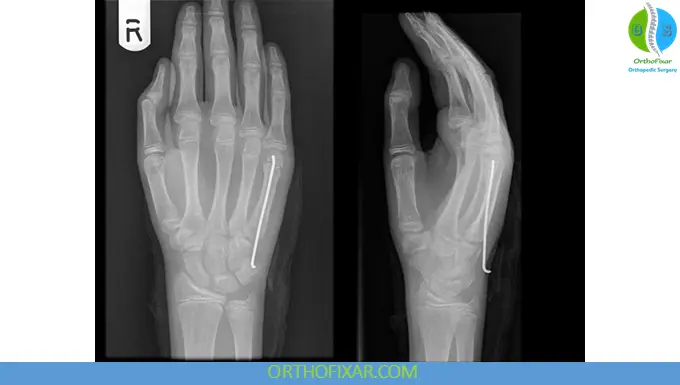

2. Surgical Management

Indications:

- Significant angulation (>40-45 degrees of angulation)

- Rotational deformity

- Open fractures

- Intra-articular involvement

- Neurovascular injury

Surgical Options:

- Kirschner wire (K-wire) fixation

- Plate and screw fixation

Surgery aims to restore alignment, prevent malunion, and improve hand function.